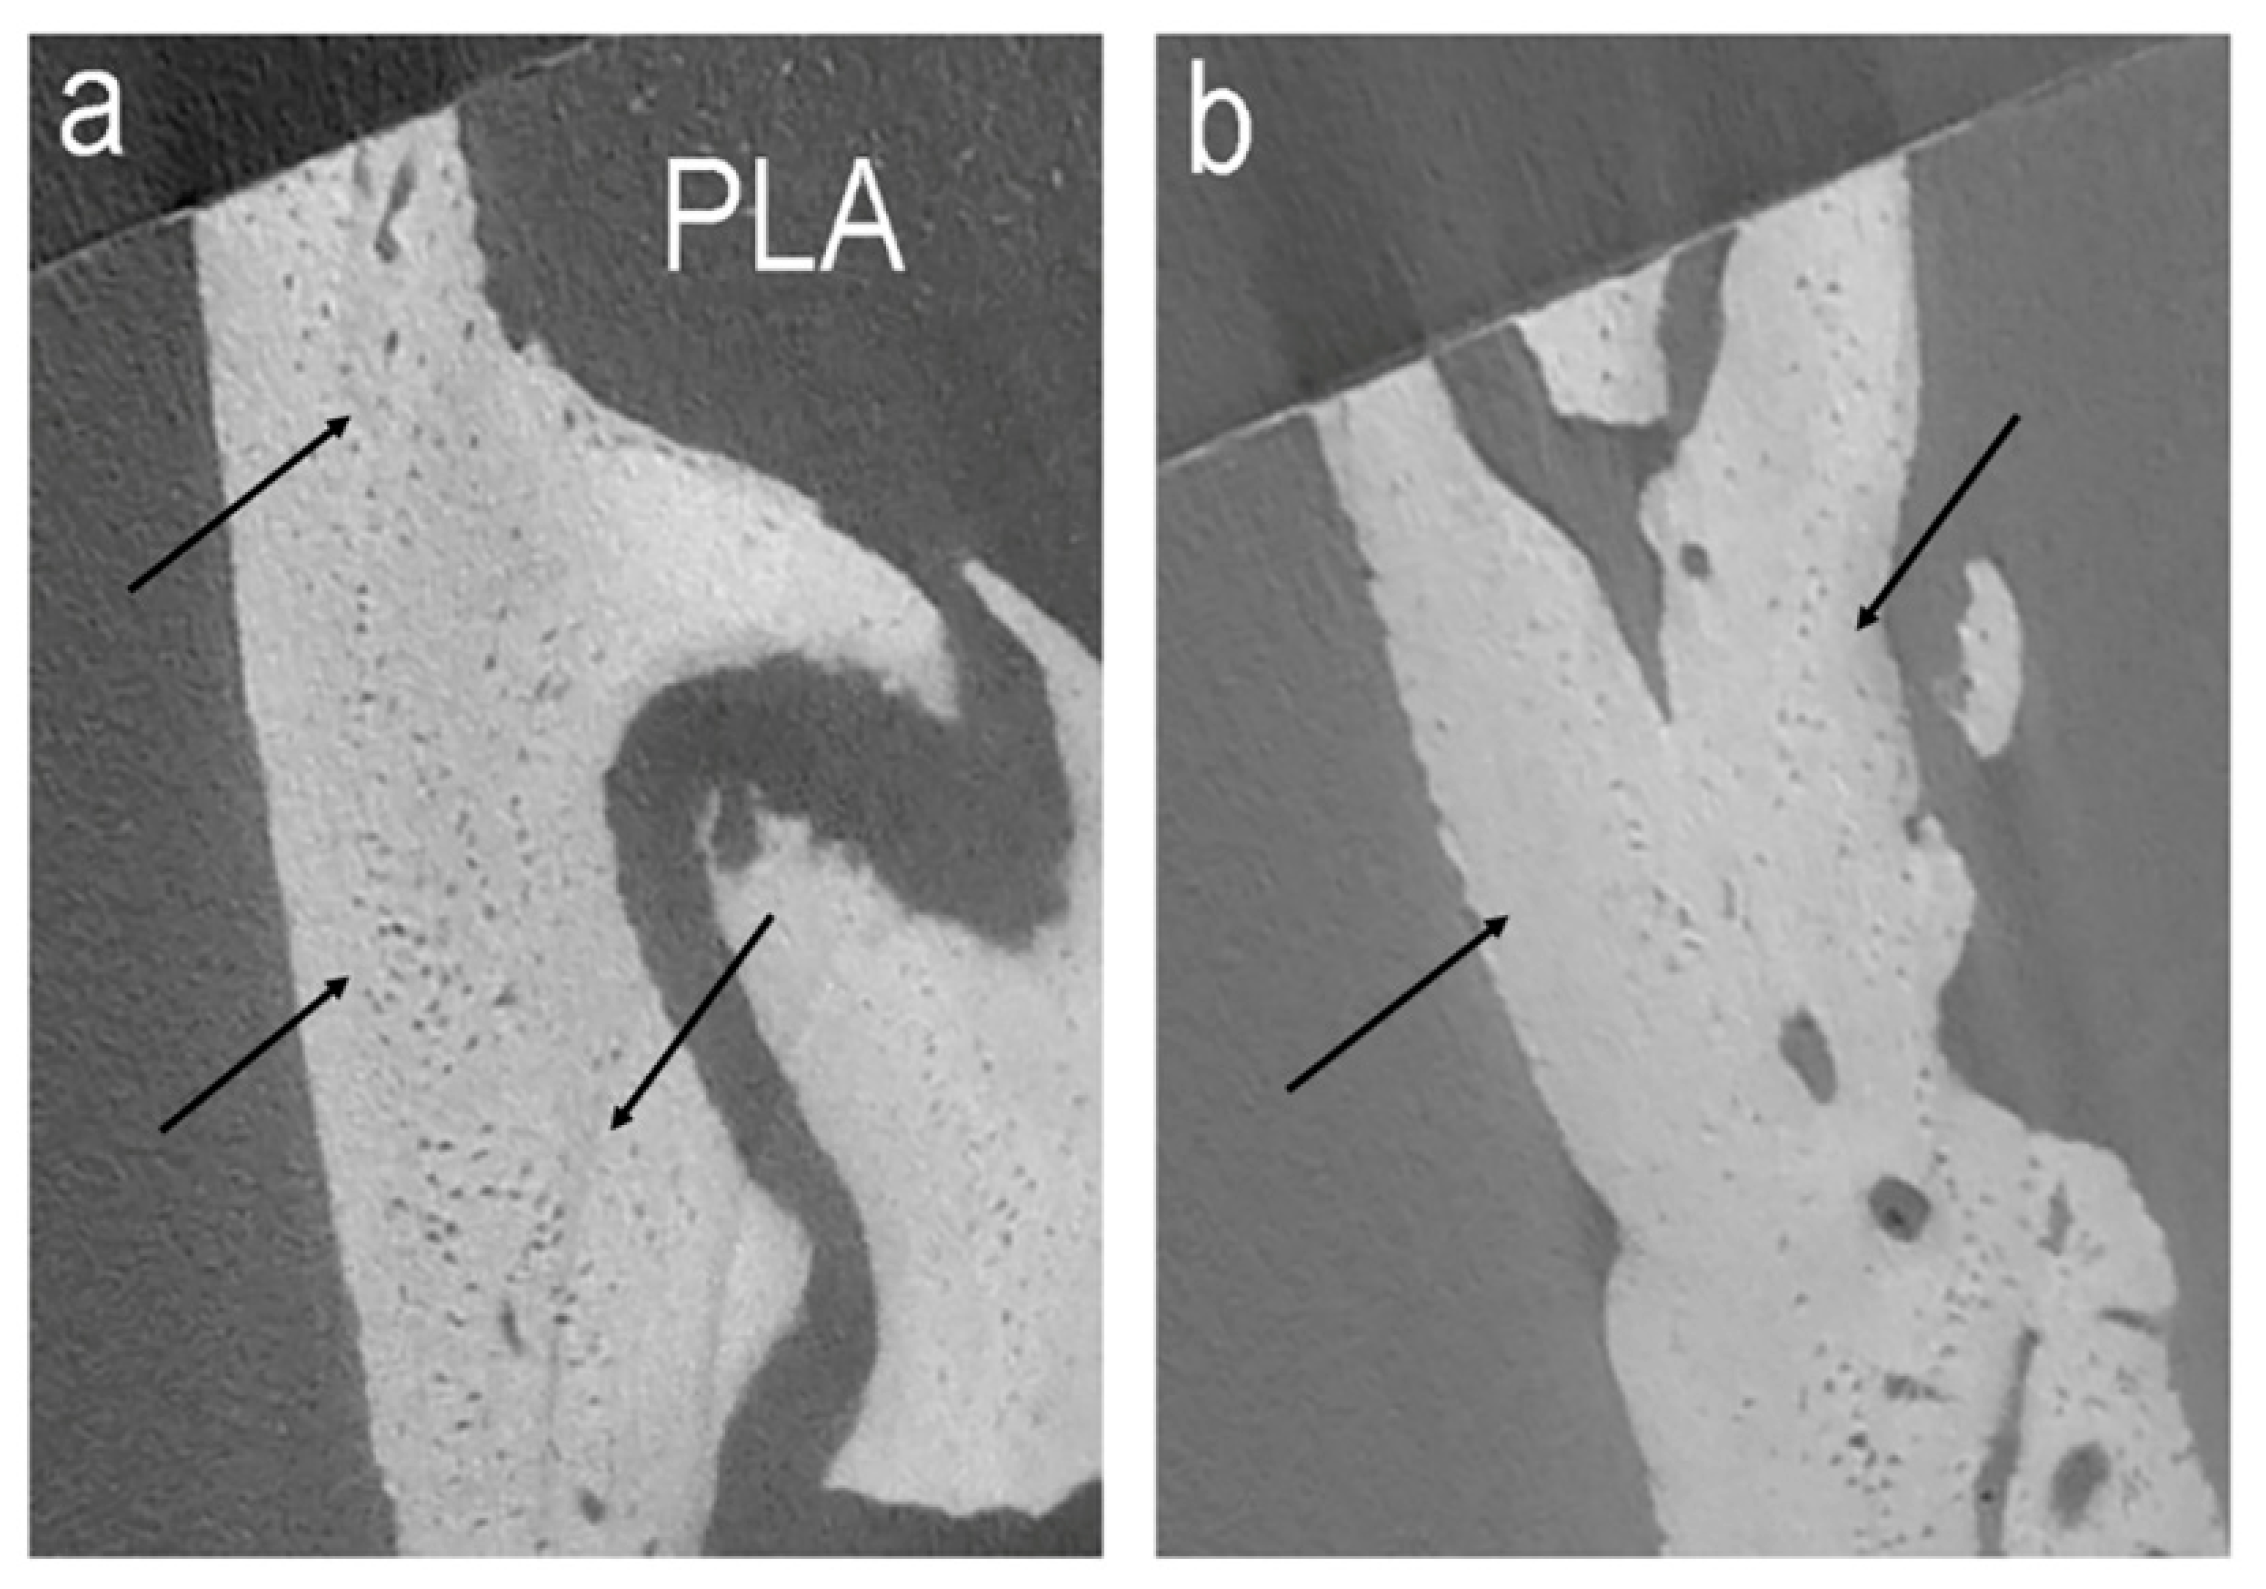

- PLA (N = 4): rats grafted with PLA;

- Diomede, F.; Gugliandolo, A.; Cardelli, P.; Merciaro, I.; Ettorre, V.; Traini, T.; Bedini, R.; Scionti, D.; Bramanti, A.; Nanci, A.; et al. Three-dimensional printed PLA scaffold and human gingival stem cell derived extracellular vesicles: A new tool for bone defect repair. Stem Cell Res. Ther. 2018, 9, 104. [Google Scholar] [CrossRef]